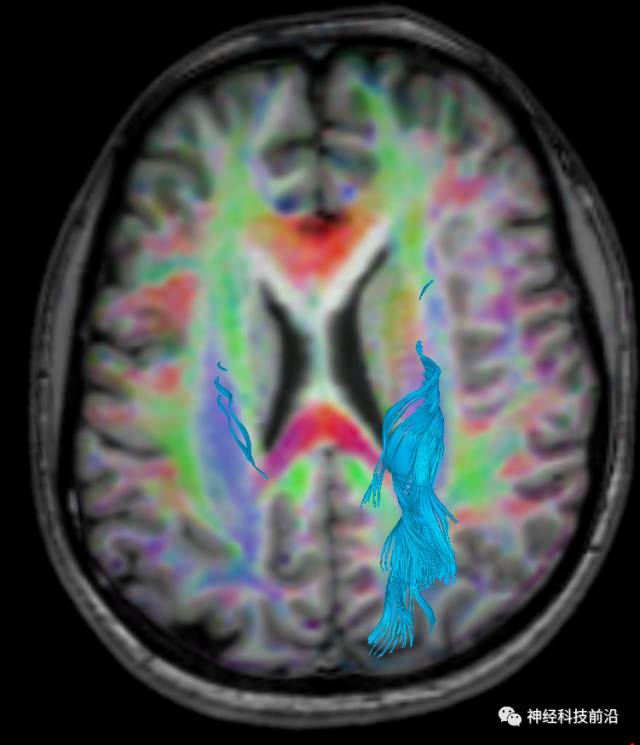

DTI原始图像与T1融合图像

下面为皮质脑桥束的走形方位